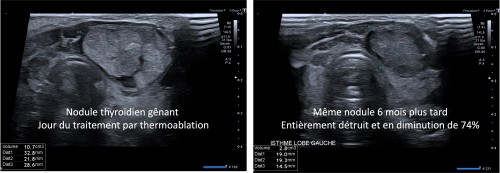

- Thermoablation par radiofréquence des nodules thyroïdiens bénins et des petits cancers de la thyroïde.